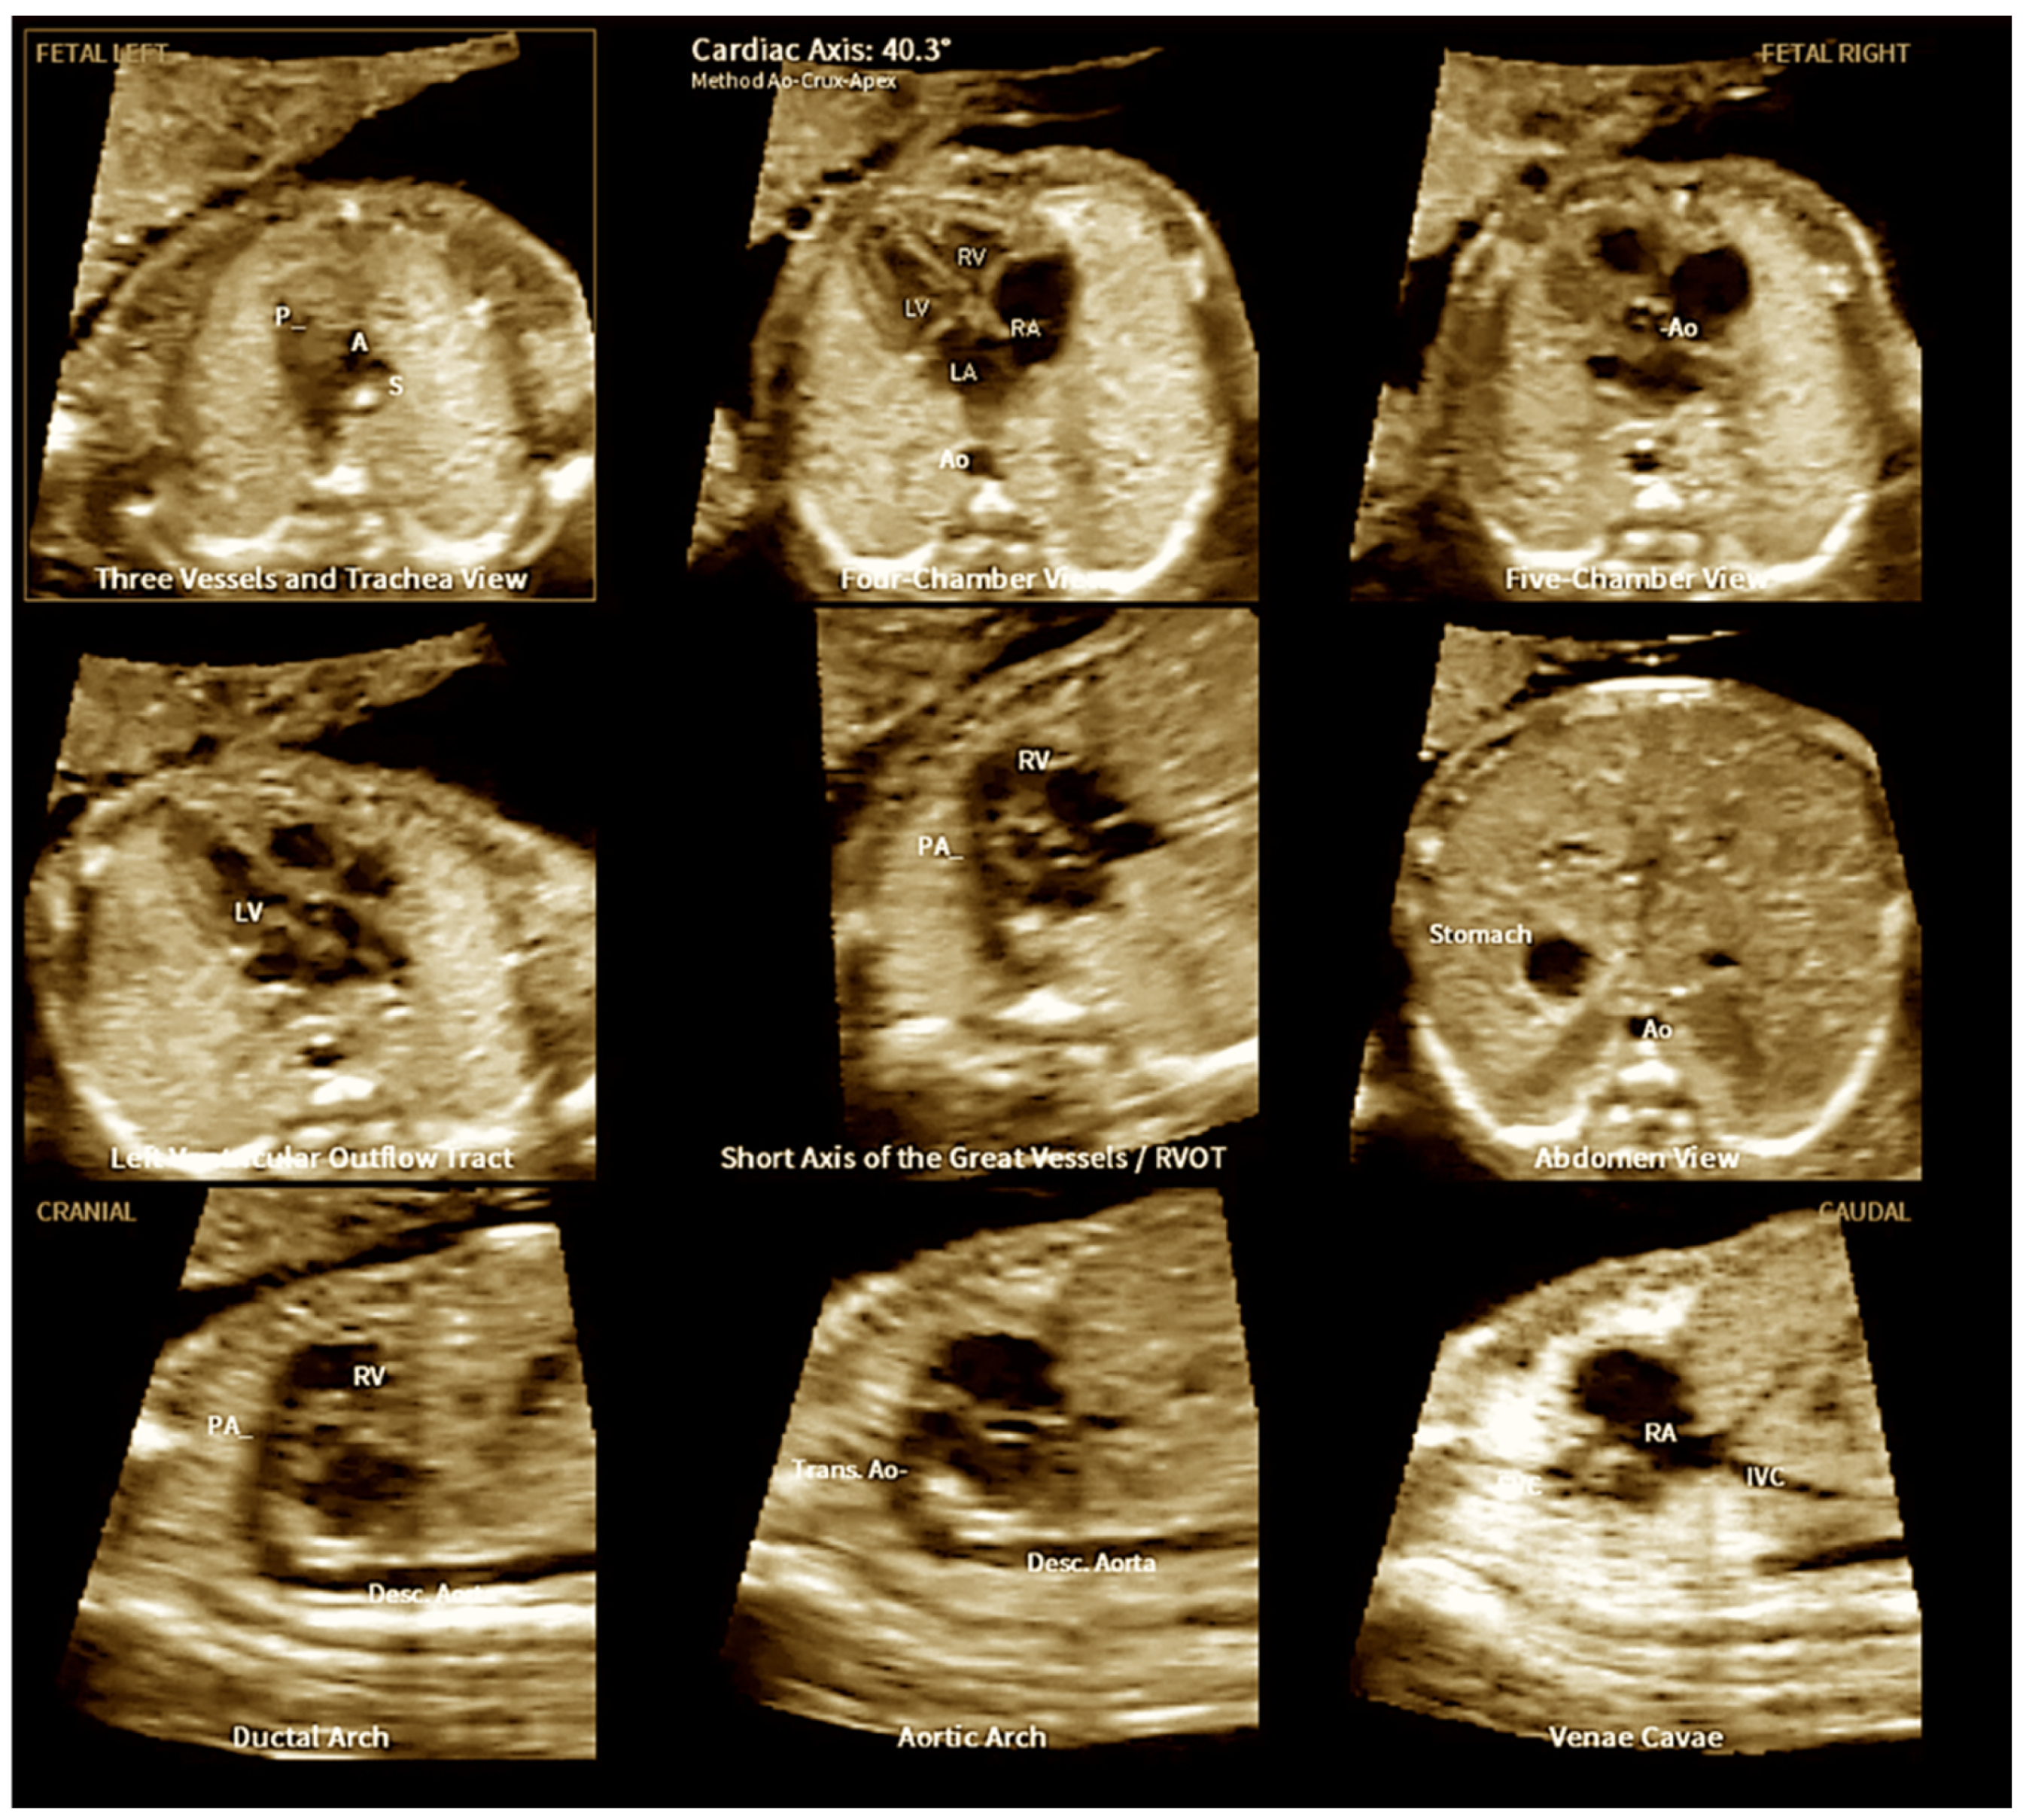

- Yeo L, Romero R. Fetal Intelligent Navigation Echocardiography (FINE): A Novel Method for Rapid, Simple, and Automatic Examination of the Fetal Heart. Ultrasound Obstet Gynecol. 2013, 42, 268–284.

- Carrillo MC, Rolo LC, Tonni G, Araujo Júnior E. Evaluation of the quality of standard fetal heart views using the FAST, STAR and FINE four-dimensional ultrasound techniques in congenital heart disease screening. Echocardiography. 2020, 37, 114–123.

- Liu K, Zhu M, Zhang YQ, Chen LJ, Dong SZ. Utility of fetal cardiac magnetic resonance imaging in assessing the cardiac axis in fetuses with congenital heart disease. Pediatr Radiol. 2023, 53, 910–919.